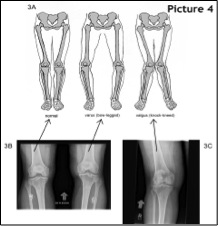

Παρόλο που τα χαρακτηριστικά των βλαισών και ραιβών γονάτων (εικ.4), τα πόδια με πλατυποδία (εικ.5) και κοιλοποδία (εικ.6) (ψηλή ποδική καμάρα), έχουν ενοχοποιηθεί στο παρελθόν σαν παράγοντες αιτίας για επιγονατιδομηριαίο πόνο, εντούτοις οι πρόσφατες μελέτες δεν έδειξαν σημαντικές διαφορές σε σχέση με τα άτομα που δεν παρουσίαζαν τα παραπάνω προβλήματα.

Αν η γωνία αυτή (εικ7) είναι μεγαλύτερη από 20 μοίρες, το σημείο επαφής και πίεσης στην επιγονατιδομηριαία άρθρωση αλλάζει, αυξάνοντας τις πιθανότητες για υπεξάρθρημα της επιγονατίδος και επιγονατιδομηριαίο πόνο.